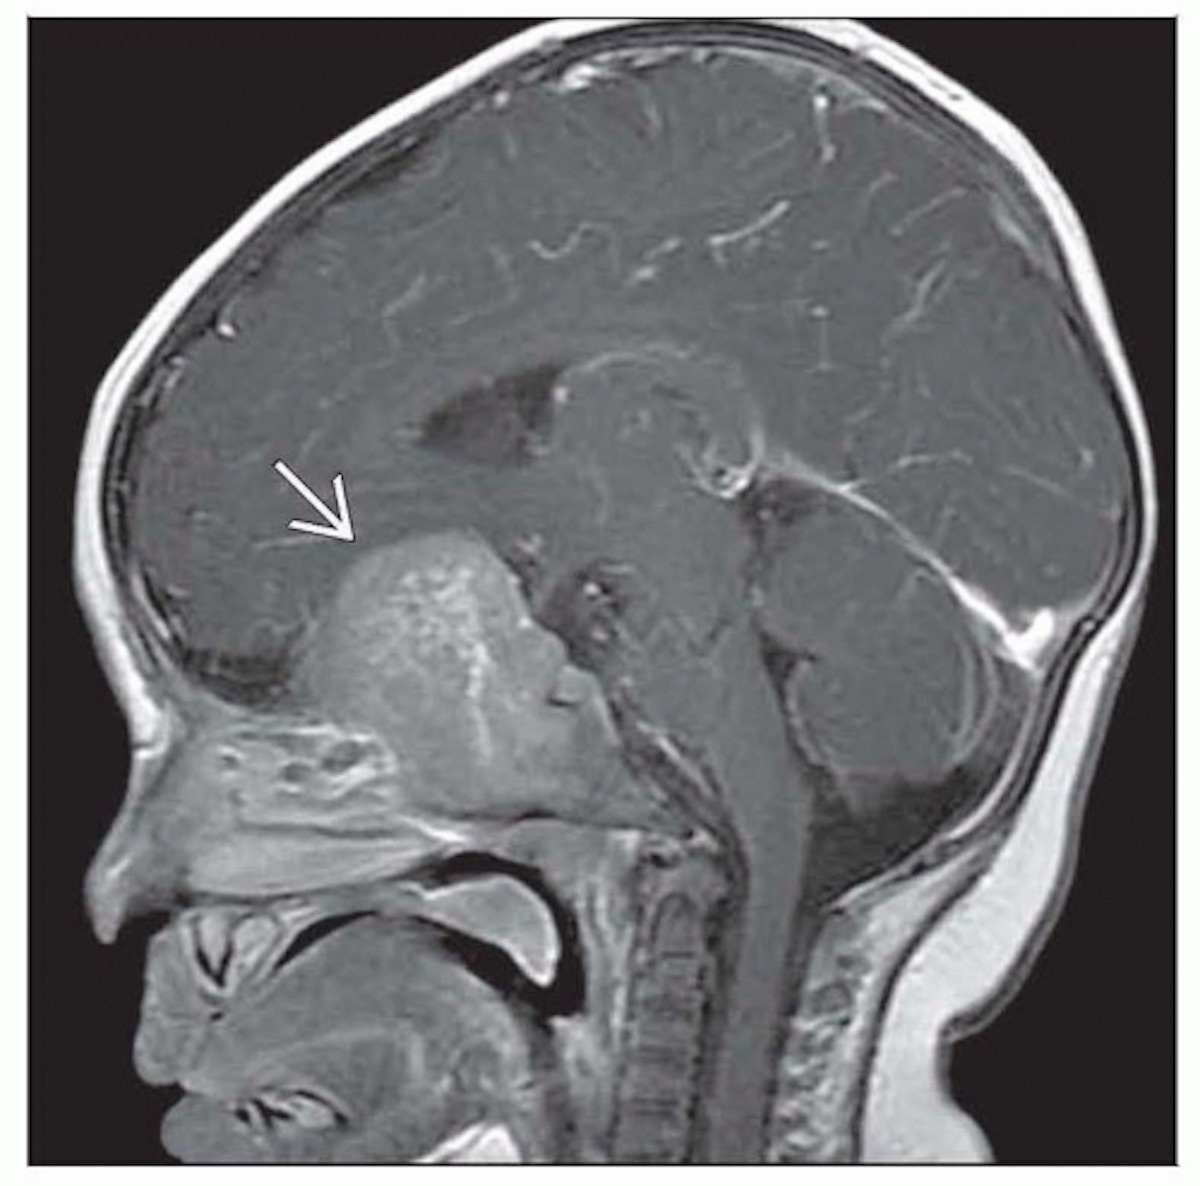

Web primitive neuroectodermal tumor (pnet) is a kind of extremely rare and highly aggressive, small round cell tumor, with poor prognosis. Primitive neuroectodermal tumor is a malignant (cancerous) neural crest tumor. Ein primitiv neuroektodermaler tumor, kurz pnet, ist eine hochgradig bösartige raumforderung, die zu den embryonalen tumoren zählt und ihren ursprung im neuronalen gewebe hat.

Names of specific pnets may be based on the tumor location. Web primitive neuroectodermal tumors (pnets) are a group of highly malignant tumors composed of small round cells of neuroectodermal origin that affect soft tissue. The overall 5 year survival rate is about 53%.

Web primitive neuroectodermal tumors are extremely rare and highly aggressive malignant small round cell tumors that arise from the primitive nerve cells of. Web primitive neuroectodermal tumor, also referred to as pnet, is a category of malignant (cancerous) tumors which appear similar under the microscope to medulloblastoma but. It gets its name because the majority of the cells in the tumor are derived from neuroectoderm, but have not developed and differentiated in the way a normal